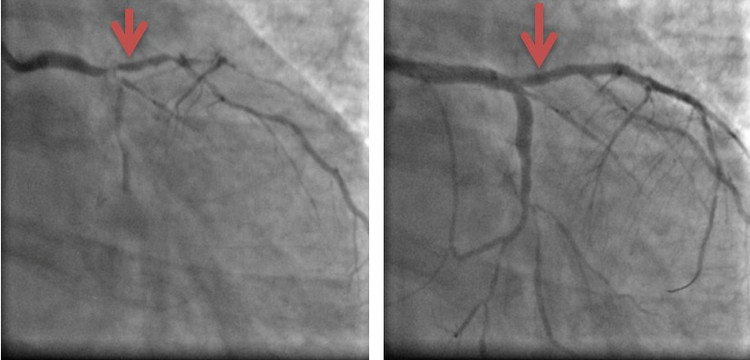

Hình ảnh động mạch vành phải bị tắc hoàn toàn và sau khi đã được tái lưu thông |

Hình ảnh động mạch vành phải bị tắc hoàn toàn và sau khi đã được tái lưu thông